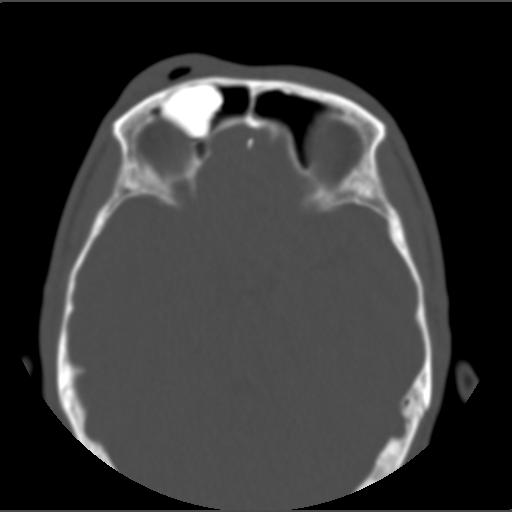

m49y外伤常规ct发现筛额窦右侧高密度块影 。

右侧额筛都内致密性高密度影,余骨皮质未见明显异常改变,右额皮下血肿伴少许积气,我想是致密影是骨瘤.

右侧额筛都内致密性高密度影,境界清楚,余骨皮质未见明显异常改变,符合骨瘤表现

右侧额筛都内致密性高密度影,境界清楚,余骨皮质未见明显异常改变,考虑额筛窦内生性骨瘤.

颅面部骨瘤一般密度致密,多发额骨及鼻窦腔壁,呈扁丘样改变.边界清楚,大部分密度均一.

此片应与验证纤维化做一区分

1、致密型骨瘤。2、右额部头皮挫裂伤。

右额窦至密性骨瘤,右额骨皮下软组织挫伤拌积气.